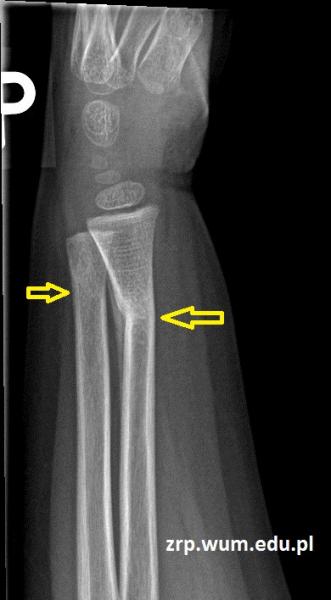

3-latek po urazie przedramienia prawego - kontrola po zdjęciu gipsu

Przypadek 60: 3-latek po złamaniu przynasad dalszych obu kości przedramienia prawego. Badanie kontrolne po zdjęciu gipsu (4 tyg. po urazie).

Rozpoznanie: Na zdjęciach RTG widoczne nawarstwienia okostnowe / odczyny naprawcze w miejscu złamania prawej kości promieniowej, z jej niewielkim kątowym ustawieniem. Niewielkie nawarstwienia okostnowe w okolicy złamania prawej kości łokciowej.